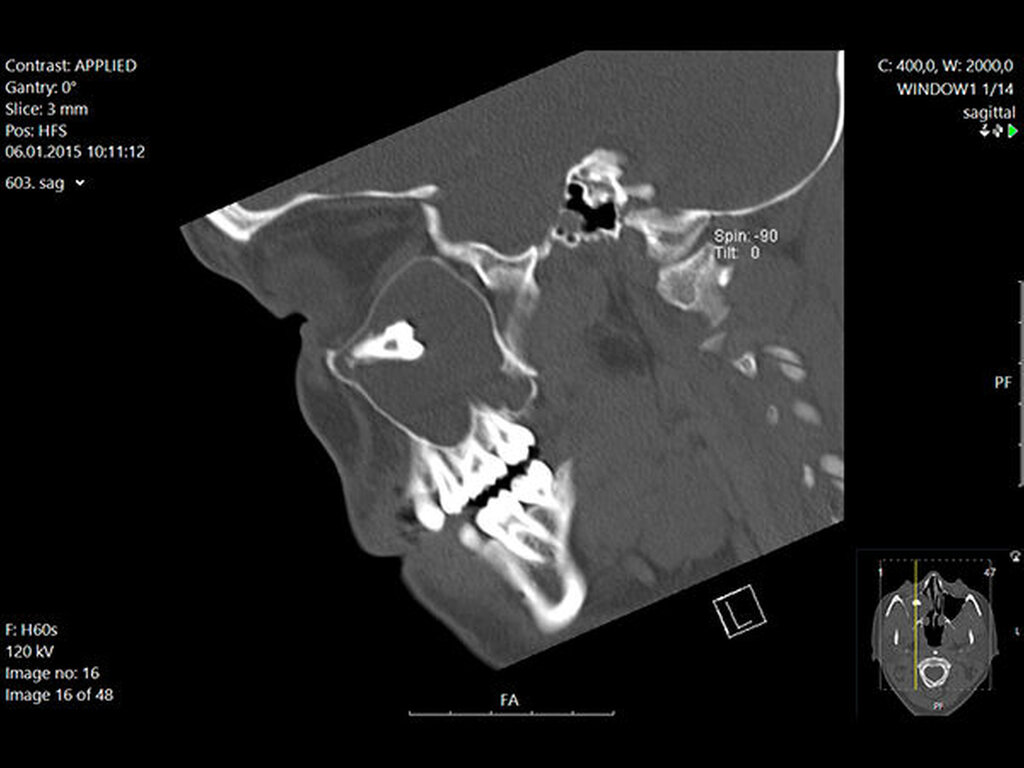

In der regionalen Klinik (Winterberg-Krankenhaus Saarbrücken) wurde zusätzlich eine kontrastmittelunterstützte Computertomografie der Nasennebenhöhlen durchgeführt (Abbildungen 2 und 3), die den Befund bestätigte und präzisierte.